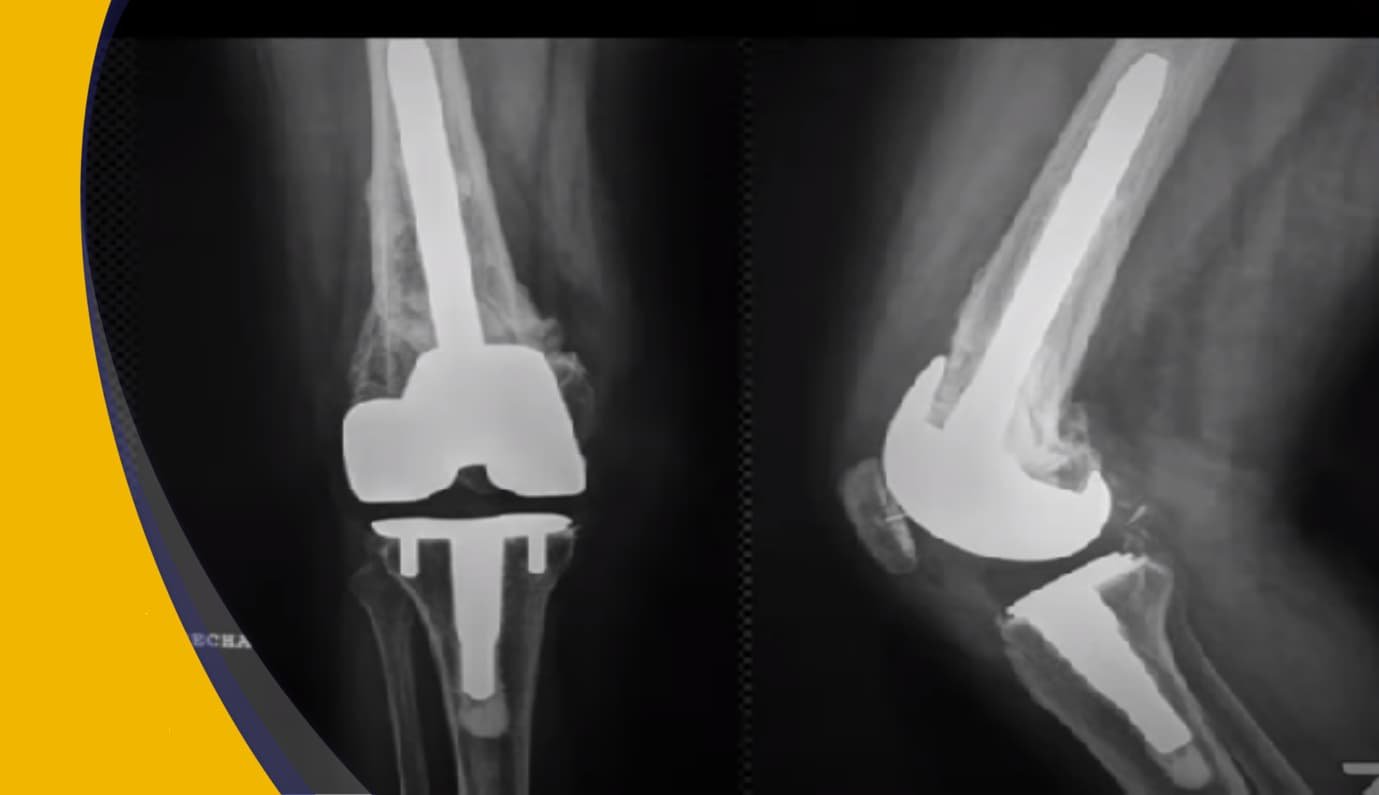

El Dr. Efraín es especialista en Cirugía Articular, además de Profesor titular Curso de Alta Especialidad en cirugía articular de cadera y rodilla y en este Webinar explica todo sobre la artroplastia de rodillas.